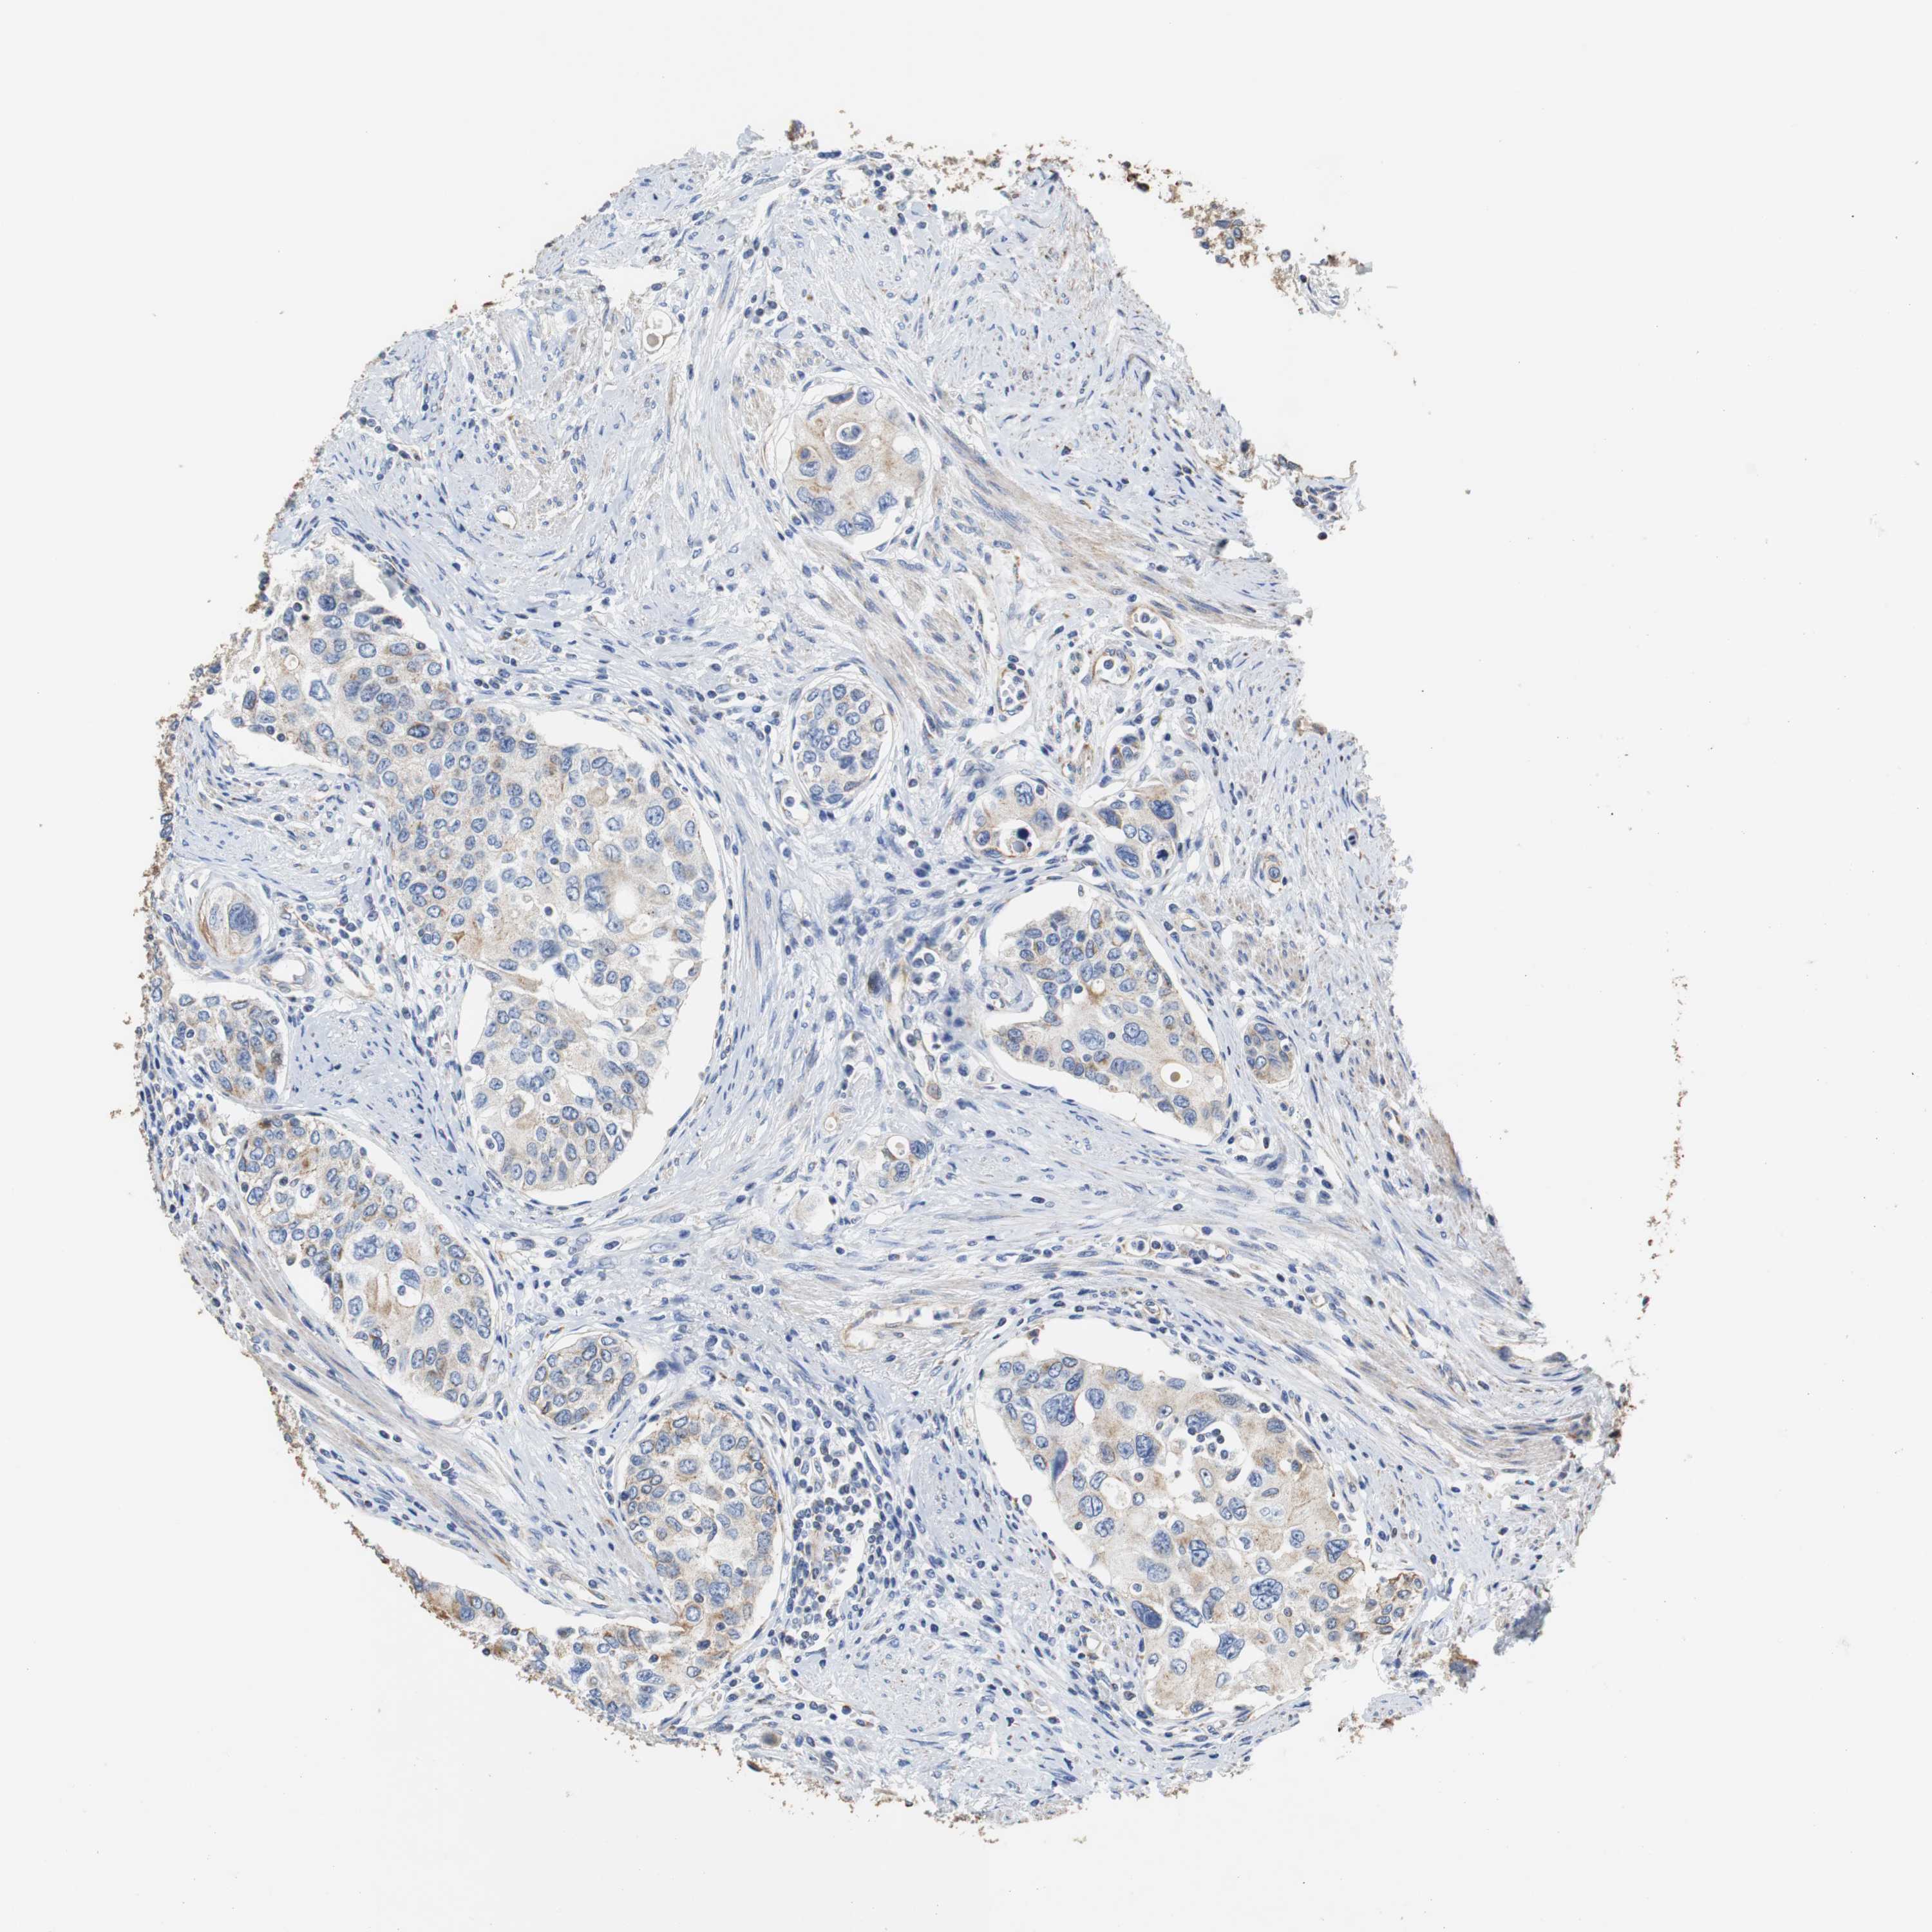

UROTHELIAL CANCER - Protein expressioni

A mouse-over function shows sample information and annotation data. Click on an image to view it in a full screen mode. Samples can be filtered based on level of antibody staining by selecting one or several of the following categories: high, medium, low and not detected. The assay and annotation is described here.

Note that samples used for immunohistochemistry by the Human Protein Atlas do not correspond to samples in the TCGA dataset.

Antibody stainingi

Antibody staining in the annotated cell types in the current human tissue is reported as not detected, low, medium, or high, based on conventional immunohistochemistry profiling in selected tissues. This score is based on the combination of the staining intensity and fraction of stained cells.

Each image is clickable and will lead to virtual microscopy that enables deeper exploration of all samples and also displays staining intensity scores, fraction scores and subcellular localization as well as patient and tissue information for each sample.

Antibody HPA006277

Antibody HPA006507

Antibody CAB017027

Staining

High

Medium

Low

Not detected

Intensity

Strong

Moderate

Weak

Negative

Quantity

>75%

75%-25%

<25%

None

Location

Nuclear

Cytoplasmic/membranous

Cytoplasmic/membranous,nuclear

Urothelial carcinoma, Low grade

Urothelial carcinoma, High grade